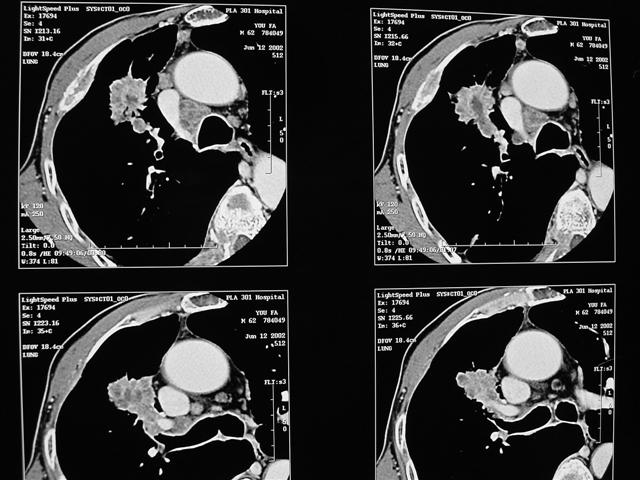

男,64岁,咳嗽、咳痰20余天,明显消瘦,x线片发现肺部阴影

1)右肺上叶前段周围型肺癌并阻塞性肺炎、右肺门及纵隔淋巴结转移、肋骨及胸椎转移。2)右肺上叶后段纤维病灶。

考虑右肺上叶前段周围型肺癌并右肺门及纵隔淋巴结肿大、肋骨及胸椎转移。